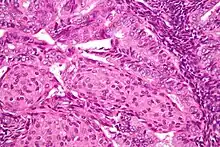

.jpg.webp)

In endometrioid adenocarcinoma, the cancer cells grow in patterns reminiscent of normal endometrium, with many new glands formed from columnar epithelium with some abnormal nuclei. Low-grade endometrioid adenocarcinomas have well differentiated cells, have not invaded the myometrium, and are seen alongside endometrial hyperplasia. The tumor's glands form very close together, without the stromal tissue that normally separates them. Higher-grade endometrioid adenocarcinomas have less well-differentiated cells, have more solid sheets of tumor cells no longer organized into glands, and are associated with an atrophied endometrium. There are several subtypes of endometrioid adenocarcinoma with similar prognoses, including villoglandular, secretory, and ciliated cell variants. There is also a subtype characterized by squamous differentiation. Some endometrioid adenocarcinomas have foci of mucinous carcinoma.[46]

The genetic mutations most commonly associated with endometrioid adenocarcinoma are in the genes PTEN, a tumor suppressor; PIK3CA, a kinase; KRAS, a GTPase that functions in signal transduction; and CTNNB1, involved in adhesion and cell signaling. The CTNNB1 (beta-catenin) gene is most commonly mutated in the squamous subtype of endometrioid adenocarcinoma.[47]